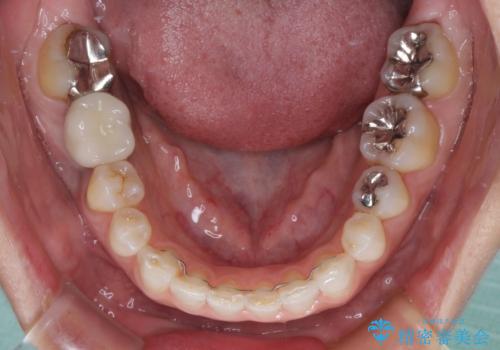

- 右下の奥歯が痛く、全体的に咬み合わせがおかしい気がするとのことで来院された患者様です。

診察したところ、上顎前歯に過剰歯があることで上顎歯列が大きくなり、上下の歯が奥歯の一部でしか咬み合っていない状態でした。

そのため右下の奥歯に強い負担が生じていて、むし歯が大きかったこともあり、抜歯が必要な状態でした。